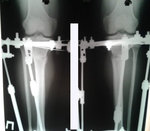

рентген в 90 дней.

Здравствуйте, Б.! Сращение идёт хорошо, но Вам ходить ещё месяц. в 120 дней ждём рентген.